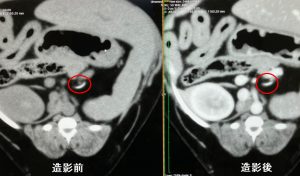

秋の健康診断として、血液検査 とレントゲン検査を実施、

その結果、肝数値(ALT )の軽度上昇と肝腫大が認められ ました 。

赤い点線が肝臓を示しています。

肝障害があって、肝臓が大きいとなれば